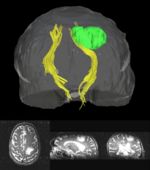

Primary brain tumors lead to changes in the diffusion properties of white matter due to edema, infiltration, tract displacement and destruction. Despite investigation of diffusion changes in white matter bordering tumors, these changes have not been quantitatively determined along the length of white matter tracts that may be affected by a tumor. The study of these tracts is especially interesting as the pattern of spread/growth of primary brain tumors is by infiltration along white matter tracts.

Clustered fibers in the region of the corticospinal tract have been used to identify regions of interest for slice-by-slice measurements of this tract's diffusion properties in normals and in tumor subjects. A pilot study (with Monica Lemmond at Harvard Medical School and Stephen Whalen and Alexandra Golby at Brigham and Women's Hospital/HMS) has demonstrated changes in tumor-affected tracts (relative to the contralateral unaffected side) beyond the apparent tumor border. A larger study is currently underway.

- Monica E. Lemmond, Lauren J. O'Donnell, Stephen Whalen, and Alexandra J. Golby.Characterizing Diffusion Along White Matter Tracts Affected by Primary Brain Tumors.